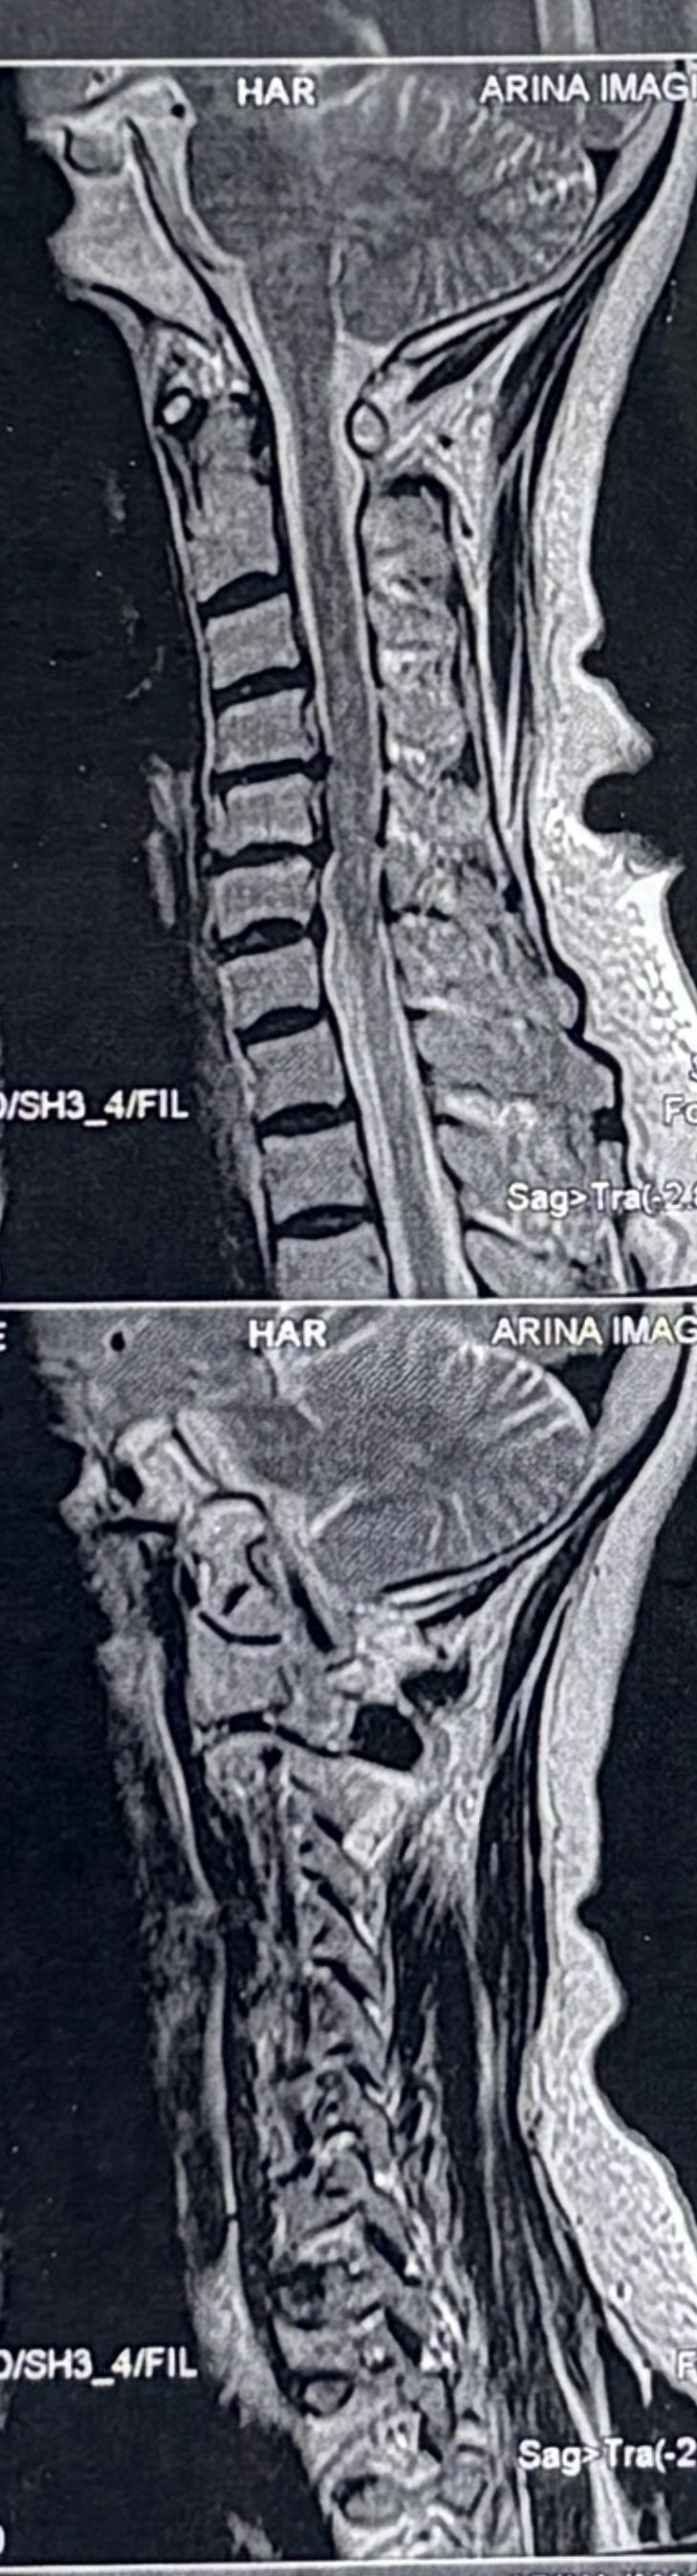

40 yrs old female patient presented to my clinic 2 hrs ago on May 18/2024 with severe neck and R upper extremity pain along C6 dematome. Had 12 sessions of PT with almost 20 percent improvement in her pain. Still has severe pain. I ordered EMG/ NCV( result showed moderate R c6 radiculopathy with no axonal loss)

Her mri is posted. i have started her treatment with acupuncture and very gentle cervical decompression. In 3 months her mri will be repeated